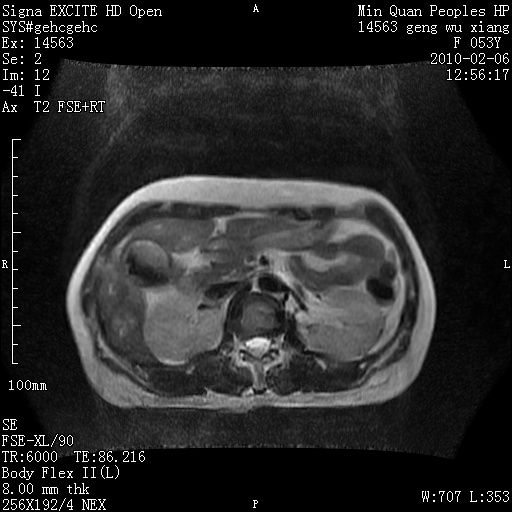

标题: MRI2762:胆道梗阻原因?

f,53y,全身黄染多日。

高位胆道梗阻 胆管癌可能性大

支持 高位胆道梗阻 胆管癌可能性大。